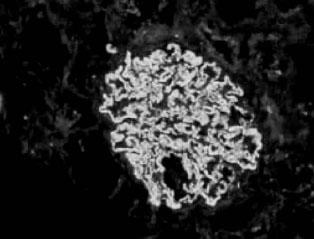

上述各期免疫荧光检查均可见IgG、C3弥漫性细颗粒沉积于小球毛细血管袢(图2—8),有时可见IgM及纤维蛋白。

图2—7 膜性肾病Ⅱ期,毛细血管基膜弥漫性增厚,钉突形成(PASM x1000)

图2—8 膜性肾病,IgG呈颗粒状沉积于毛细血管壁(免疫荧光 x400)